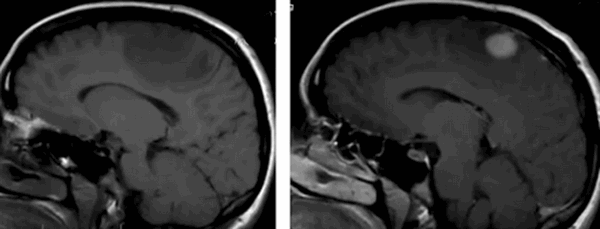

До- и постконтрастное изображение злокачественной опухоли головного мозга

С помощью МРТ при раке мозга выявляют локализацию опухоли, степень ее инвазии в соседние структуры, особенности кровоснабжения, стадию заболевания и наличие метастазов. Для получения дополнительных сведений, сканирование проводят в различных последовательностях (Т1, Т2, FLAIR, диффузно-взвешенное и пр.), в нативном режиме и после контрастирования.